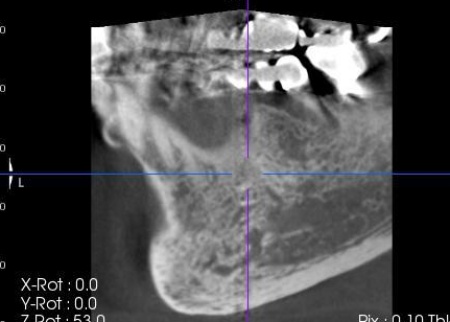

次にCT検査を行い、骨の量や神経の位置を確認したうえでインプラント治療の計画を立てています。

完成した治療計画をもとに、インプラントをあごの骨に埋める手術を実施しました。

歯やあごの骨の状態を詳しく調べるためレントゲン検査を行った結果、右下の奥歯2本(第2小臼歯、第1大臼歯)は、歯根が縦方向に割れている可能性が高いと考えられました。

しかし、レントゲン画像だけでは歯根の状態を正確に判断することはできません。